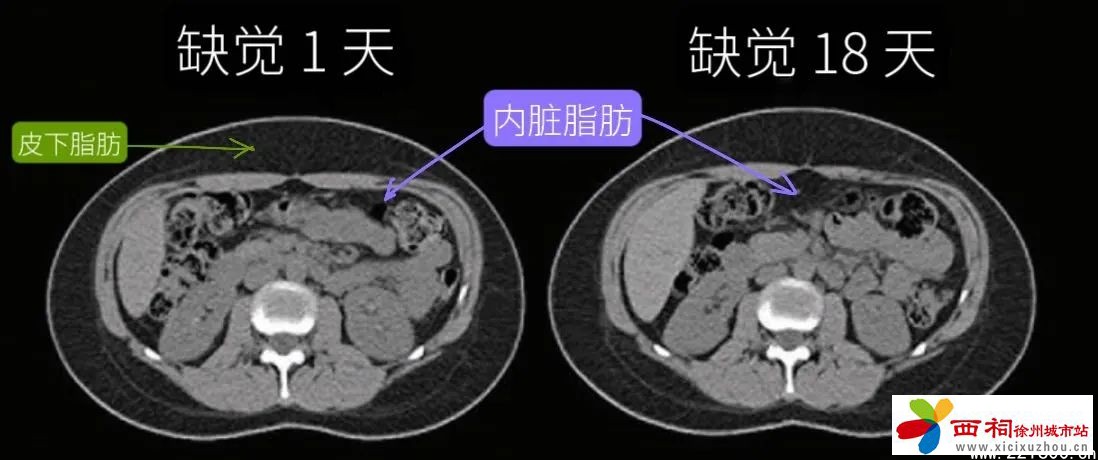

02缺觉长出来的脂肪可能是“内脏脂肪”

都是胖肚子,却有胖“皮下”和胖“内脏”的区别。科学家在发现“缺觉会导致肚子长胖”后,又进一步分析了内脏脂肪的占比,得到了这样的结论:

• 睡饱睡足、不缺觉的人,即使不小心吃多、稍稍发胖一些,也主要是存在皮下,内脏脂肪面积没有出现明显增加。

• 反观缺觉的人,不仅更容易胖,内脏脂肪面积也足足增加了11%,就算是缺觉后立马补觉也无济于事。

缺觉时脂肪存储机制变化,更容易把脂肪转移到肚子内部,变成“内脏脂肪”,包围各大内脏器官,损伤心血管、影响身体代谢。内脏脂肪增多,和很多疾病风险增加相关,例如高血压、中风、心脏病、糖尿病等,还可能脑部萎缩,影响大脑信息处理的能力,甚至多个癌症风险同时飙升。